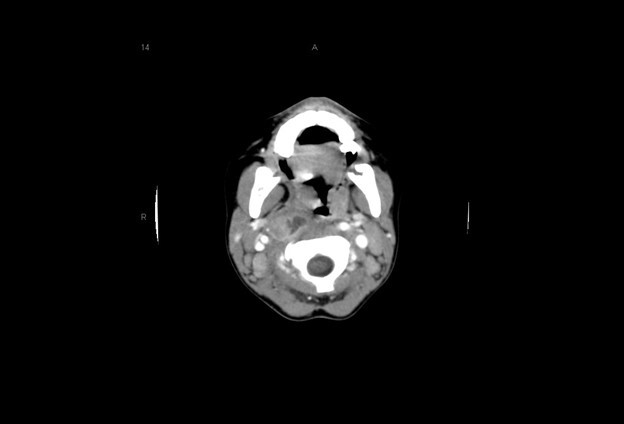

The initial evaluation should include an attempt to visualize the posterior pharynx, which may show a mass or bulging enlargement of the anterior cervical lymph nodes. Complete blood count may show a leukocytosis with left shift; blood cultures are rarely positive in children with RPAs. Lateral neck radiographs will show a widening of the retropharyngeal space. At the level of C3, the prevertebral soft tissues should measure less than two-thirds of the width of the vertebral body. If the soft tissues measure > 7 mm at C2 or 14 mm at C6, if air-fluid levels are seen in the tissues, or if there is loss of the normal cervical lordosis due to muscle spasm, RPA should be highly considered.24 (See Figure 2.) Computed tomography of the neck can make the diagnosis definitively, aid with visualization of the vessels of the neck, determine any extension of the abscess, and help plan for surgical intervention and drainage.27 (See Figure 2.) Clindamycin is the current drug of choice for initial treatment of RPAs, given the increased incidence of MRSA.26 Children with respiratory compromise may require operative drainage by otolaryngology.

Figure 2. Retropharyngeal Abscess |

![]() |

The first image is a lateral neck radiograph showing widening in the prevertebral soft tissues, raising concern for a retropharyngeal abscess. The second image is a computed tomography of the same retropharyngeal abscess. Images courtesy of Stephen John Cico, MD, MEd. |